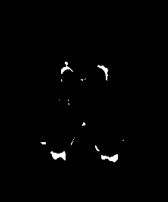

The white matter lesions in a total of 15 subjects were manually delineated by a neuroradiologist to be used as ground truth lesion segmentations for evaluation of the proposed method. We compared the proposed method with three state-of-the-art segmentation methods: 1) A supervised tissue segmentation developed for the AGES-Reykjavik data set, created with an artificial neural network classifier in the four dimensional intensity space defined by FLAIR, T1-w, T2-w and Proton Density weighted images and trained on 11 manually annotated subjects[12]; 2) the patch-based Subject Specific Sparse Dictionary Learning (S3DL) method [19], which takes FLAIR and T1-weighted images as input for lesion segmentation as well as three manually annotated atlases; and 3) the whole brain segmentation method FreeSurfer [17], which only takes a T1-weighted image as input, but is included in the comparison due to its widespread use. For each of the methods above, the preprocessing steps were as described in their associated publications. A visual comparison of the methods is shown for two subjects in Figure 2. The top row in Figure 2 demonstrates that SegAE can accurately segment lesion boundaries of the test image with the largest lesion load. The bottom row shows an example of a subject with a smaller lesion load but with enlarged ventricles.

| FLAIR image | Supervised | FreeSurfer | S3DL | SegAE | Manual |

|---|---|---|---|---|---|

![]() |